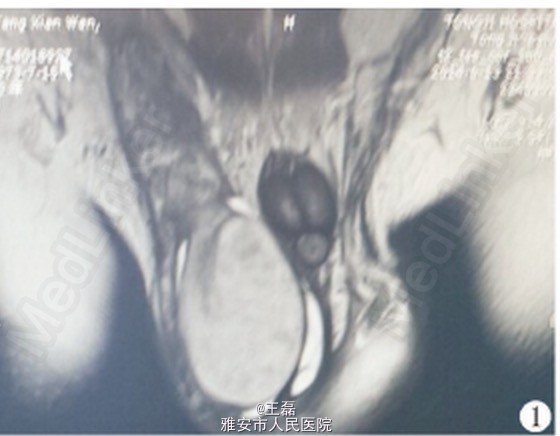

查体:双侧腹股沟区未触及肿大浅表淋巴结,右侧睾丸明显肿大,沉重感,触之质硬,无压痛,右侧精索明显增粗。 彩超示右侧精索明显增粗,右侧睾丸明显增大,大小约5.5 cm×4.2 cm,实质回声尚均,进一步行MRI检查,结果示右侧睾丸及附睾异常信号增大,右侧睾丸大小58 mm×44 mm,T1 WI 信号大致均匀,T2 WI 信号稍欠均匀,呈散在点状稍低信号改变,DWI扫描信号均匀,右侧附睾精索明显增粗并呈显著不均匀强化改变,考虑肿瘤(图1)。AFP、HGB均在正常范围。

术前诊断:右侧睾丸肿瘤可能。2014年6月20日行右侧睾丸根治性切除术,术前快速行细胞学穿刺,示黏液性腺癌可能,术中完整切除睾丸及精索,术后病理示右侧睾丸、附睾及睾丸旁结缔组织黏液腺癌,结合临床,符合直肠黏液腺癌术后转移(图2)。术后患者于肿瘤内科进一步行化疗,术后3个月随访,患者局部无复发,远处无转移。